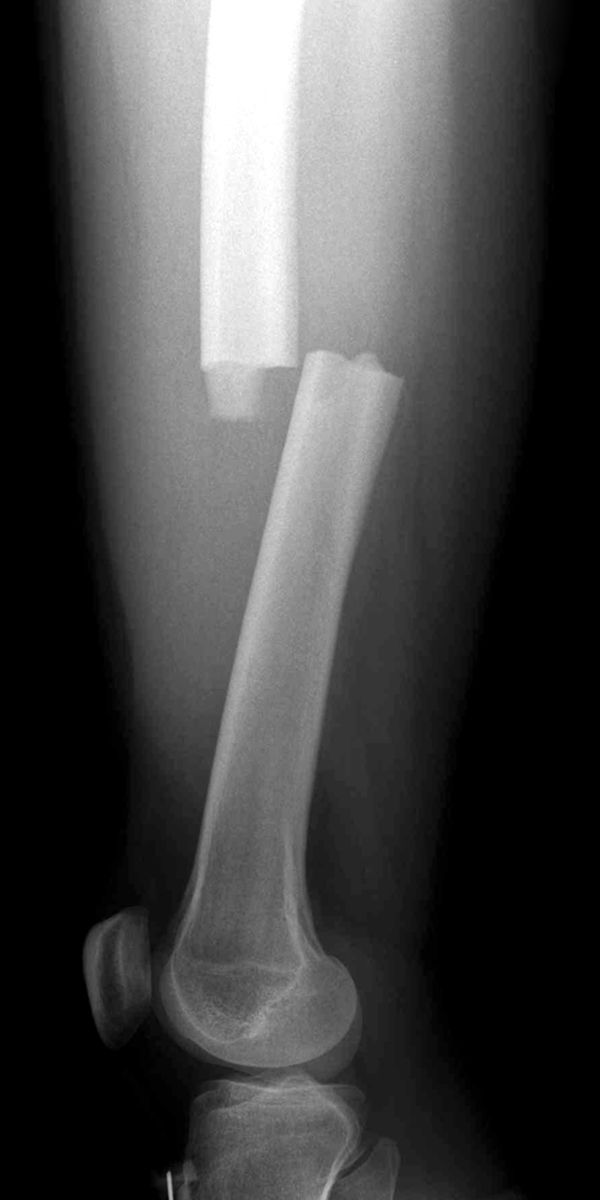

Transverse femoral shaft fracture

X-ray shows a transverse fracture of the femur. The break is a straight horizontal line across the shaft.

Reproduced from JF Sarwak (ed): Essentials of Musculoskeletal Care, ed 4. Rosemont, IL. American Academy of Orthopaedic Surgeons, 2010.